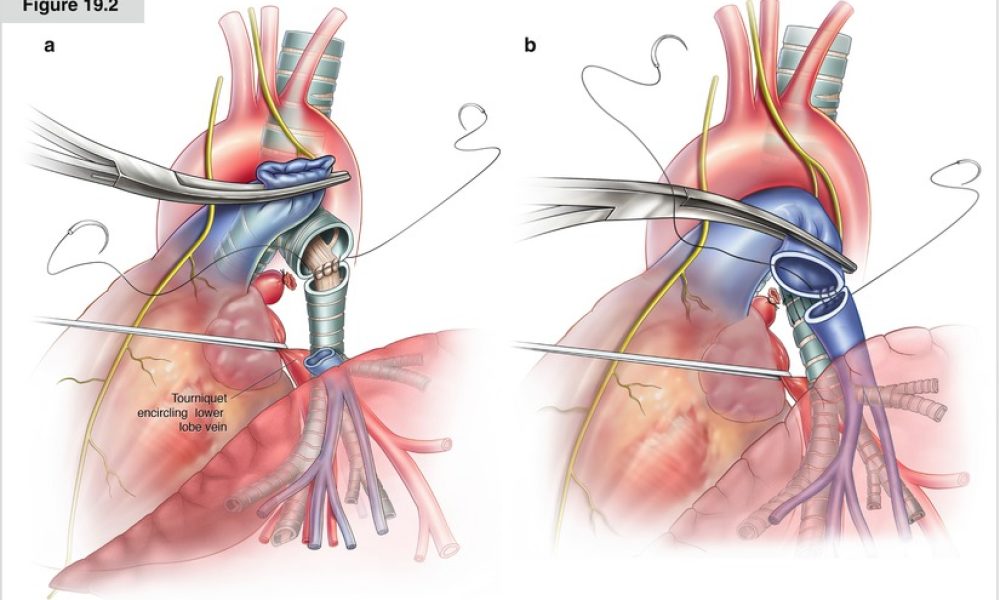

Innovative Oncology Services

Our Services

Oncology Services